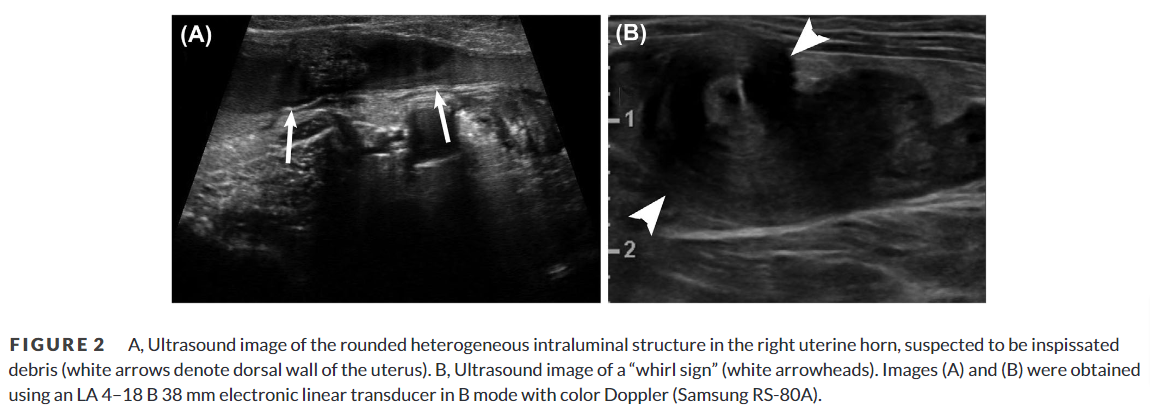

방사선 사진처럼 자궁염전이 발생하면 실제로 대형의 종괴성 병변으로 보이고 초음파 검사에서 cyst 양상으로 보인다. 이번 논문에서는 doppler 사진을 첨부하지 않아 검사의 완결성이 아쉬웠다.

과거 본인의 경험으로 꼬여있는 부분의 doppler 양상이 동맥부의 회오리 양상의 주행상이 보여 자궁 염전으로 의심했던 것, CT상에서 조영제가 주행하는 동맥이 회오리 상으로 보였던 것을 볼 때 그런 특이적 영상이 첨부되었으면 좋았을 것으로 판단된다.